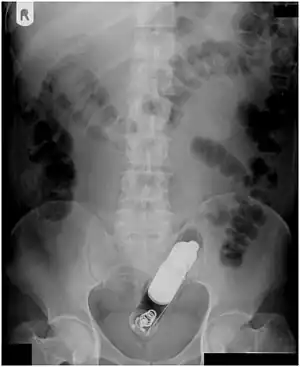

Vibrator stuck in the rectum can be seen on this abdominal X-ray.